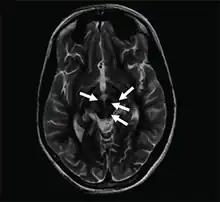

Axial T2-weighted MRI of the brain at the level of the midbrain showing the characteristic ‘face of the giant panda’ sign, with normal red nuclei and substantia nigra (pars reticulata) against a background of hyperintensity in the tegmentum, as well as hypointensity of the superior colliculi | |

The face of the giant panda sign, panda sign of the midbrain or double-panda sign is a characteristic "panda's face" appearance in magnetic resonance imaging (MRI) images of people with Wilson's disease. Along with Kayser–Fleischer rings, the sign is helpful in diagnosis.[1]